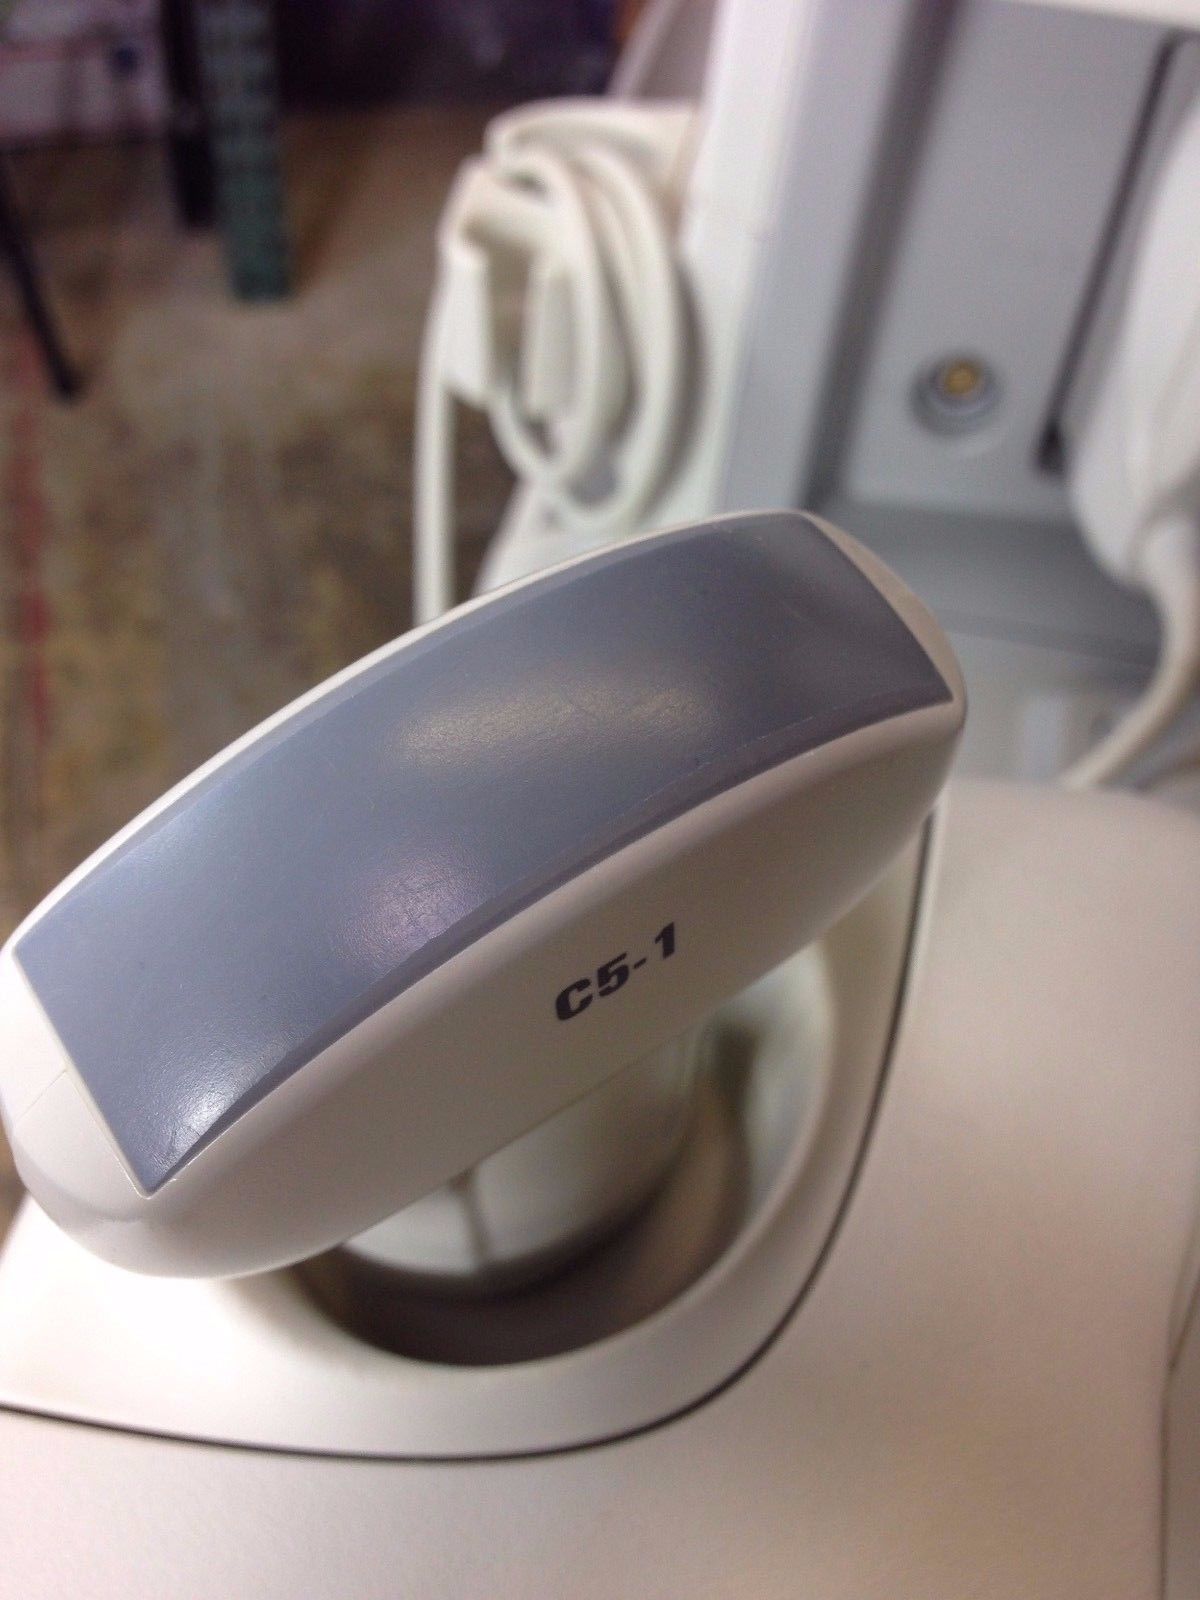

Philips Probes

DIAGNOSTIC ULTRASOUND MACHINES FOR SALE